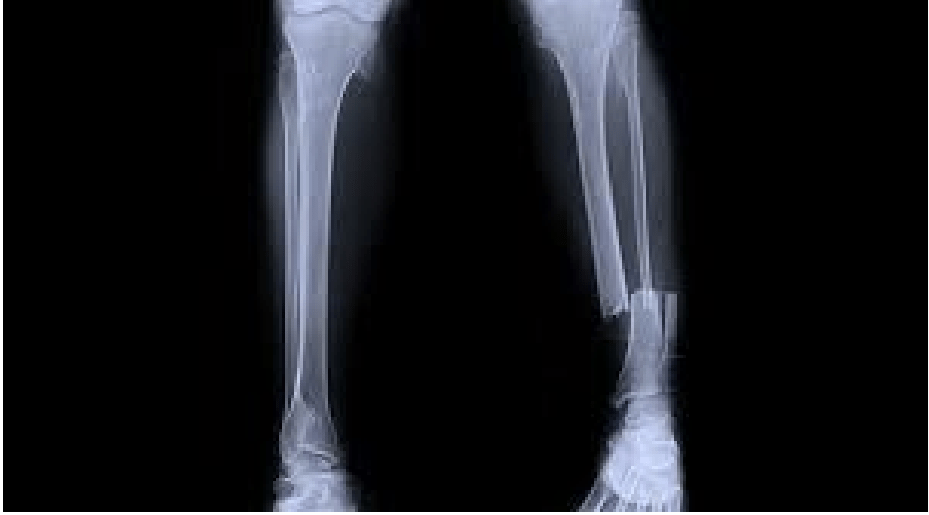

Seorang perempuan, 52 tahun, dibawa ke UGD RS dengan keluhan luka pada betis kanan dialami sejak 30 menit yang lalu akibat ditabrak motor saat hendak menyeberang jalan. Pemeriksaan fisik didapatkan luka ukuran 5cm x 3cm, tampak tulang pada bagian depan betis kiri, deformitas, udem dan hematom.

Apakah struktur anatomi yang terlibat dan apa kelainannya?

Fraktur Regio Cruris (1/3 distal Os. Tibia dan Os. Fibula)